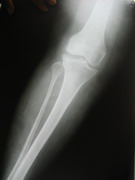

KNEE JOINTS

Knee Joints Case A

Knee Joint Replacement Knee Joint Replacement Knee Joint Replacement